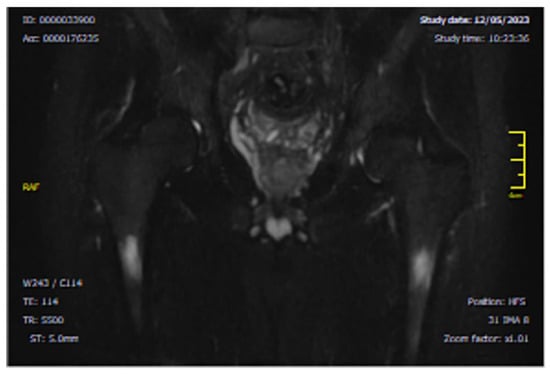

- CASE 1: A CML patient under dasatinib and imatinib treatment

- CASE 3: 66-year-old patient with imatinib therapy